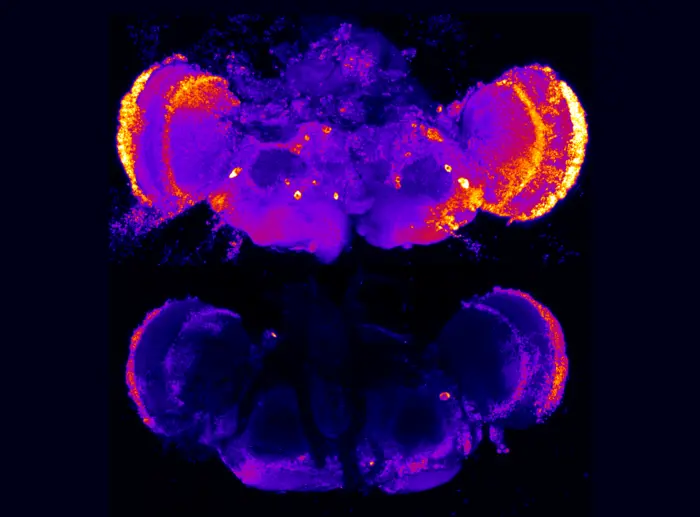

The researchers then evaluated the role of heparan sulfate-modified proteins in an animal model of Alzheimer's, a fruit fly with deficits in a presenilin protein. Presenilin mutations cause early onset disease in humans and likewise in fruit flies; defective presenilin causes cell death and brain degeneration. In flies with deficits in presenilin, reducing the function of heparan sulfate chains suppressed the death of neurons and corrected other cell defects as well. These results are directly relevant to recent human genetics research, the researchers said.